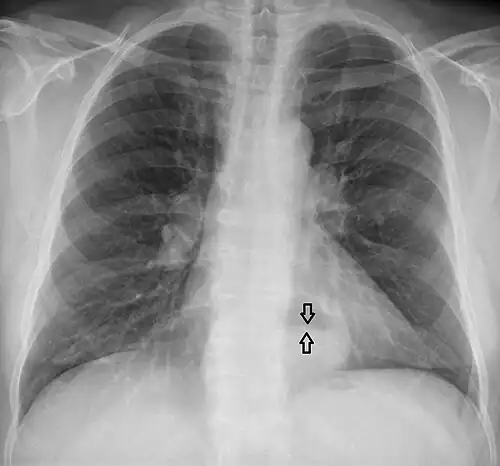

The diagnosis of a hiatal hernia is typically made through an upper GI series, endoscopy, high resolution manometry, esophageal pH monitoring, and computed tomography (CT). Barium swallow, as in the upper GI series, allows the size, location, stricture, and stenosis of oesophagus to be seen. It can also evaluate the oesophageal movements. Endoscopy can analyse the esophageal internal surface for erosions, ulcers, and tumours.

Meanwhile, manometry can determine the integrity of esophageal movements and the presence of esophageal achalasia. pH testing allows the quantitative analysis of acid reflux episodes. A CT scan is useful in diagnosing complications of hiatal hernia, such as gastric volvulus, perforation, pneumoperitoneum, and pneumomediastinum.[8]